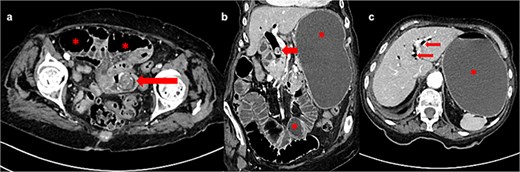

(a) Axial CT image shows gallstone in jejunum (arrow) and dilated bowel loops proximally (asterisk); (b) frontal CT image shows dilated stomach and bowel loops (asterisk) and gallstone in dilated common bile duct (arrow); (c) axial CT image shows pneumobilia (arrows) and fluid-filled and dilated stomach (asterisk).

An 88-year-old lady was admitted to our institution due to vomiting for 4 days and hematemesis on admission. The patient was icteric, hypotensive, with a distended abdominal wall and periumbilical pain on palpation. Her past medical history included permanent atrial fibrillation on warfarin, hypothyroidism, and chronic kidney disease. Laboratory testing revealed leukocytosis (leucocytes 13.3 × 109/L), normal hematocrit (0.36 L/L), elevated C-reactive protein level (CRP 89 mg/L), INR >6.0, glomerular filtration rate of 25 ml/min/1.73 m2, elevated bilirubin level (total bilirubin 57 μmol/L; reference range 3–20) as well as elevated hepatic aminotransferases [alanine aminotransferase 76 U/L (reference range 10–36), aspartate aminotransferase 113 U/L (reference range 8–30), gamma glutamyl transferase 54 U/L (reference range 9–35), alkaline phosphatase 87 U/L (reference range 64–153)]. Abdominal computed tomography (CT) scan showed intestinal obstruction in the jejunum caused by a gallstone, a gallstone in the dilated bile duct, stomach/jejunal dilatation and hepatic pneumobilia (Fig. 1). The patient received prothrombin complex concentrate, vitamin K, and other resuscitative measures before undergoing emergency surgery via median laparotomy. Intraoperatively, the small intestine was distended orally from the incarcerated 3 × 3 cm gallstone at 50 cm from the Treitz ligament and with subsequent tiger-stripe ischemic changes of the jejunum proximal to stone impaction (Fig. 2). Additionally, a cholecystoduodenal fistula and a 15-mm gallstone in the common bile duct (CBD) were found. The cholecystectomy and duodenal defect repair were performed. The gallstone was extracted from the CBD via choledochotomy and T-drainage. The ischemic part of the small intestine was resected, the gallstone was removed, and intestinal continuity was restored. Histopathology confirmed hemorrhagic necrosis of the resected intestine. After successful treatment, the patient was discharged home. One year after the surgery, the patient remained in good general health.